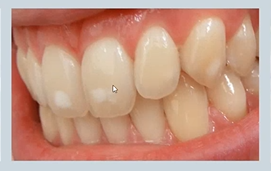

abnormal colour of teeth - what causes banding?

tetracycline (antibiotic) during odontogenesis (pregnancy/ very young children)

abnormal colour of teeth - what causes mottling?

fluorosis - excess fluoride